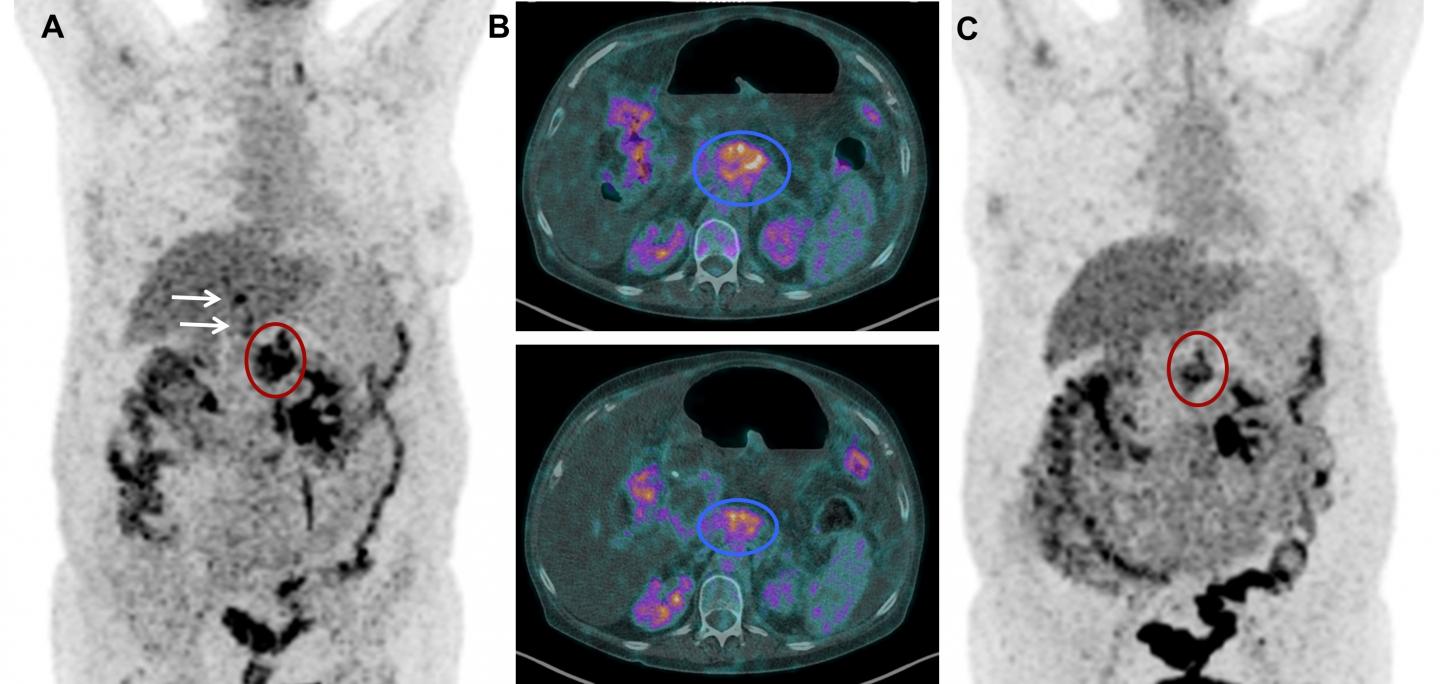

For this study, 6 patients with confirmed metastatic ductal pancreatic adenocarcinoma, who had exhausted all other treatment options, received 177 Lu-3BP-227 as salvage therapy. Scintigraphy and single-photon emission computed tomography was used with computed tomography (SPECT/CT) to determine the tumor uptake and the patients' eligibility for treatment. If the patient's condition allowed, 18 F-FDG positron emission tomography (PET)/CT imaging was performed 8-12 weeks after therapy to determine treatment efficacy.

177 Lu-3BP-227 was well tolerated by all patients, with the most severe adverse reaction a reversible grade 2 anemia. One patient experienced significant improvement of symptoms and quality of life--surviving 13 months from diagnosis and 11 months from the start of 177 Lu-3BP-227 therapy.